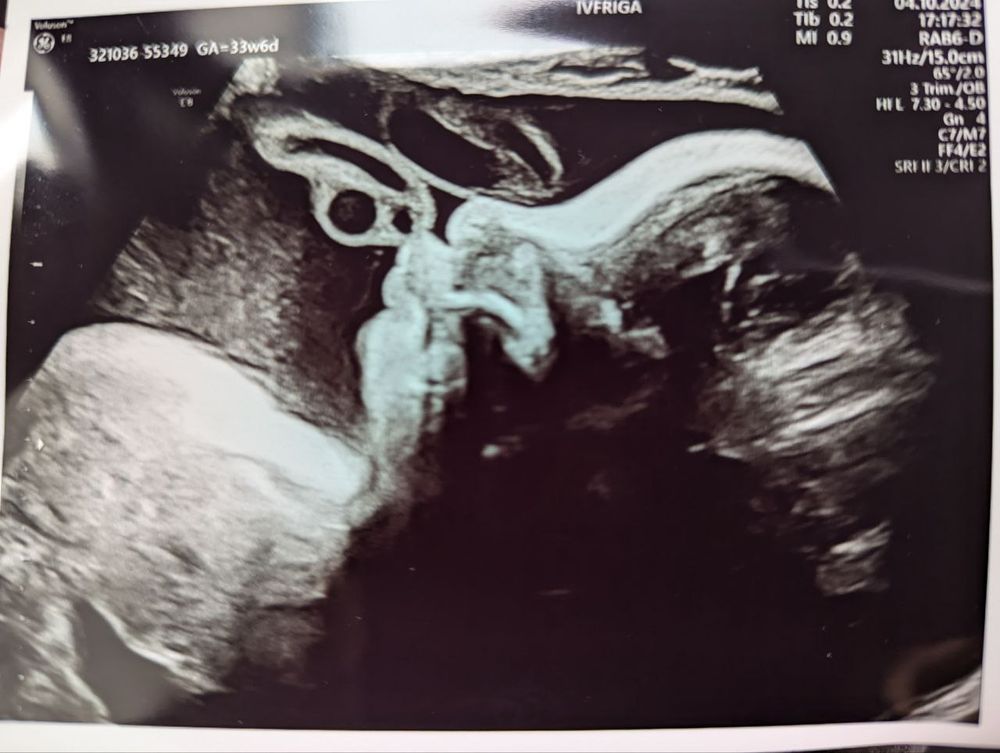

Тревоги на 34 неделе

Екатерина, спасибо большое❤️ Маловесным его не считают: вес 2210, голова больше срока (мы с мужем оба головастики), объем живота по сроку. И ноги до недавнего времени были по сроку. Но на поздних стадиях уже, видимо, всплывает генетика, вариативность, вот это все